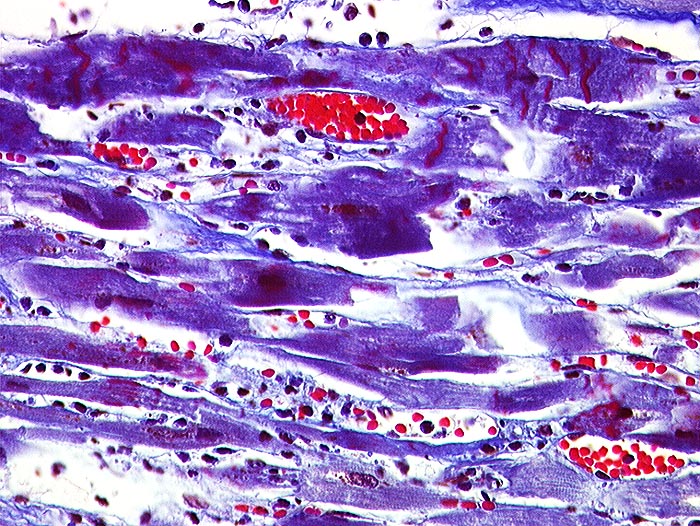

Akuter Myokardinfarkt: Kontraktionsbänder

Quer zu den Myozyten verlaufende rot gefärbte Kontraktionsbänder. Granulozytäres Infiltrat rechts im Bild.

Kontraktionsbänder sind nach 30 Minuten, zelluläre Infiltrate nach minimal 3 Stunden sichtbar. Kontraktionsbänder entstehen, wenn das hypoxisch geschädigte Myokard sich noch kontrahiert, aber nicht mehr relaxieren kann.